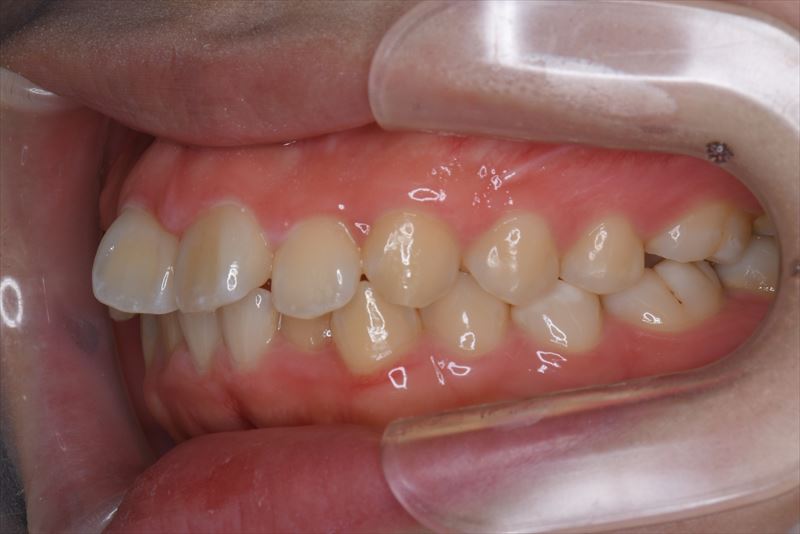

治療後

- 口唇の突出を気にされて来院いたしました。Eラインより口唇の突出、オトガイ部の緊張を認めました。アンカースクリューを用いて前歯の牽引を行うことによって良好な側貌となりました。治療途中で遠方に引っ越されたため来院が困難となり治療期間が延びてしまいましたが、患者様のご協力もあり無事に治療を終えることができました。